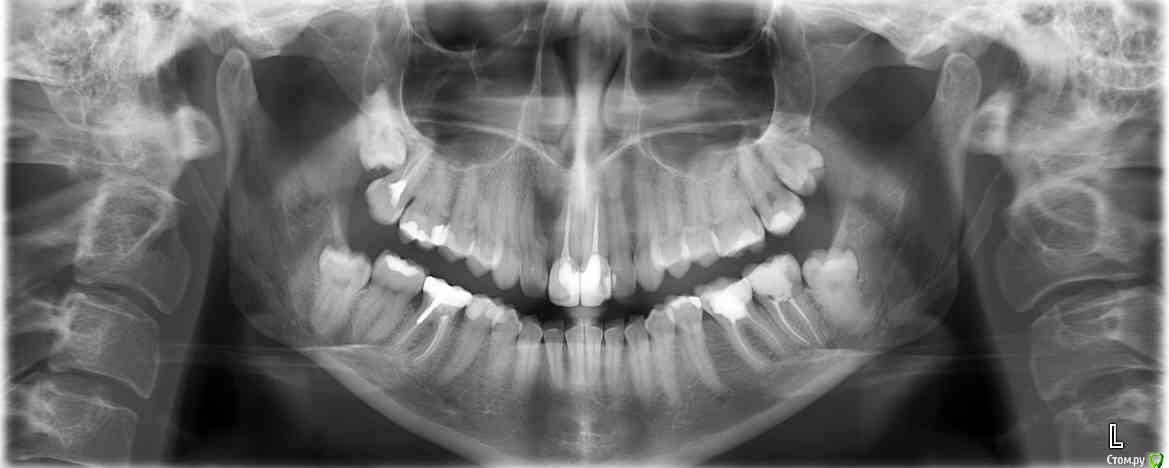

olga1985 Опубликовано 24 октября, 2016 Автор Поделиться Опубликовано 24 октября, 2016 прикладываю прошлогодний панорамный снимок до удаления зубов мудрости верхних и пломбирования переднего зуба с кистой, что киста уменьшается. заранее спасибо! Ссылка на комментарий